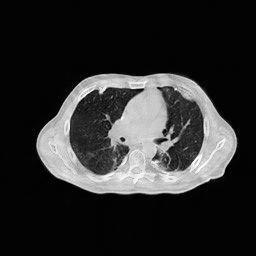

IV-E1 Rotation

The few-view CT reconstruction experiment is replicated, utilizing an identical test image rotated by degrees to simulate a rudimentary pose alteration of the patient. The reconstruction performances are shown in Fig.9, and the reconstruction results corresponding to views are shown in Fig.10. A similar experiment is also conducted under the limited-angle condition, yielding similar results.

IV-E2 Quantum Noise

To evaluate the efficacy of the proposed algorithm under conditions of reduced dosage, the previously described reconstruction experiments are replicated utilizing sinogram data contaminated with noise following a Poisson distribution. The mean count of X-ray photons detected by the th detector can be expressed as:

In this experiment, a multiplication factor denoted by cm was employed. This factor corresponds to an energy level of 80 keV, which approximates the mean energy of the beam utilized in a diagnostic CT scan conducted at a voltage of 120 kVp [54]. Throughout the experiment, , the blank measurement, is assigned values ranging from to , which correspond to sinogram SNR (dB) values of . It is worth mentioning that analogous experiments were conducted under both few-view and limited-angle scenarios, with the proposed method demonstrating a marked superiority over other methods across all conditions. This enhancement, however, is primarily attributed to the exceptional performance of the proposed method under sparse-measurement circumstances, rather than an increased resistance to noise. To facilitate an equitable comparison, the results displayed in Fig.11 are solely derived from the full-view scenario, which encompasses an angular range of with one view per degree. It is worth mentioning that this experiment solely focuses on the resilience of the RBP-DIP framework itself against noise, thus not employing any existing methods such as total variation regularization and DeepRED [42] for noise mitigation. However, these methods can be easily integrated into the RBP-DIP framework, as it shares a similar workflow with DIP.

(a) ASD-POCS (19.92dB/0.76)

(b) RBP-DIP (23.82dB/0.88)

(c) DIP (21.88dB/0.80)

(d) MED50 (15.61dB/0.42)